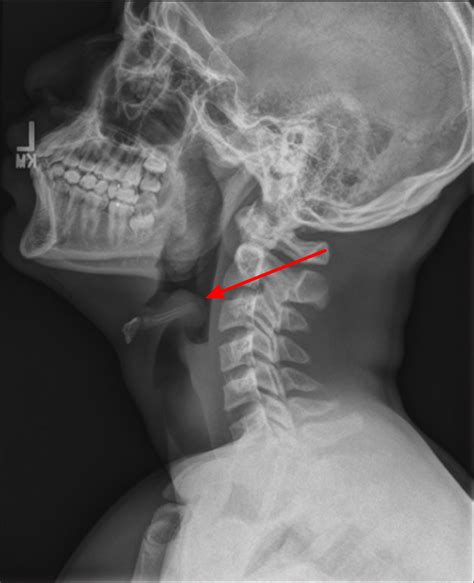

Radiological Identification: The Thumbprint Sign

The Thumbprint Sign Epiglottitis is observed on a lateral soft tissue neck X-ray. Under normal conditions, the epiglottis appears as a thin, wispy shadow. In cases of acute epiglottitis, the inflamed tissue projects posteriorly and superiorly, creating a rounded, dense, soft-tissue opacity that resembles the distal phalanx of a human thumb. Hence, it is commonly called the "thumbprint sign."

Medical teams should also be aware of the "False Negative" potential. Because the epiglottis may not always appear as a distinct thumbprint—especially in early stages or due to poor radiographic technique—the absence of the sign does not equate to the absence of disease. Trusting clinical instincts is paramount when diagnostic tests do not align with the patient’s physical appearance.